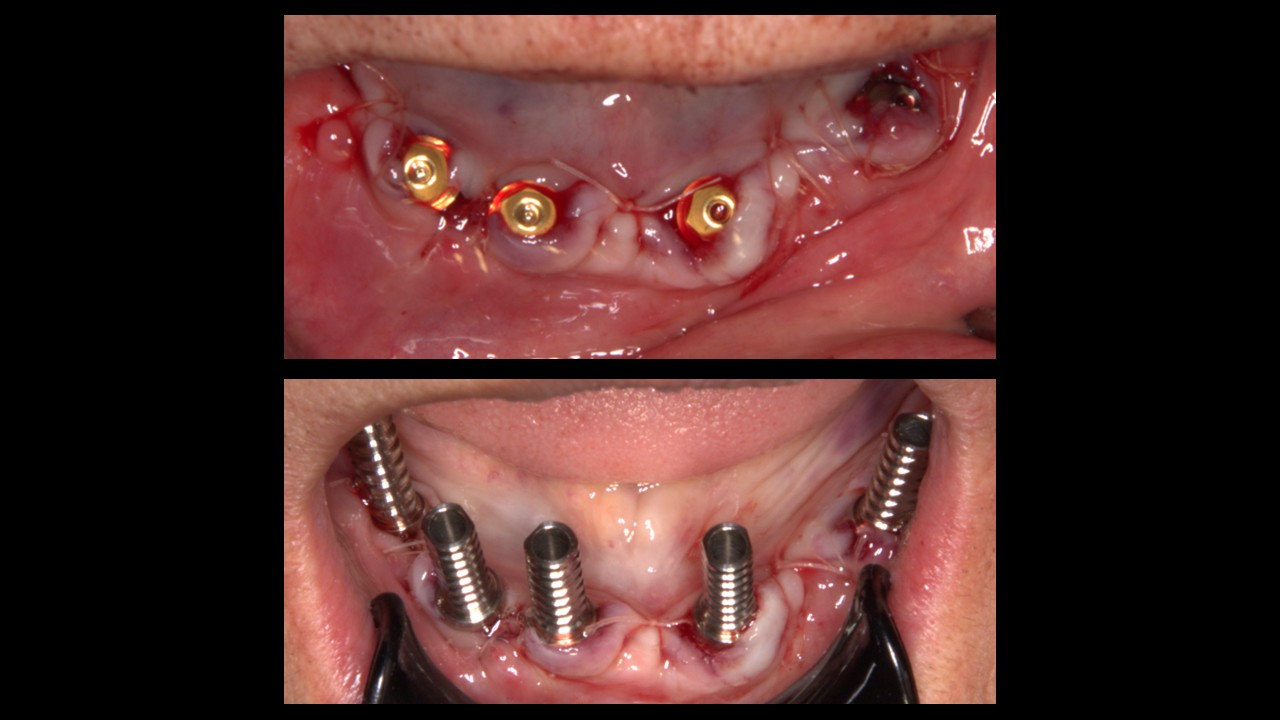

• Prueba de estabilidad primaria en IOI que serán cargados.

• Instalación de pilares multiunit en IOI que serán cargados. Prueba de coincidencia con pilares temporales en provisorio.

• Implantes dentales Osstem TSIII Superficie SOI Ø4.0x8.5mm (#1), Ø4.0x10mm (#5), Ø3.5x10mm (#2, #3, #4).